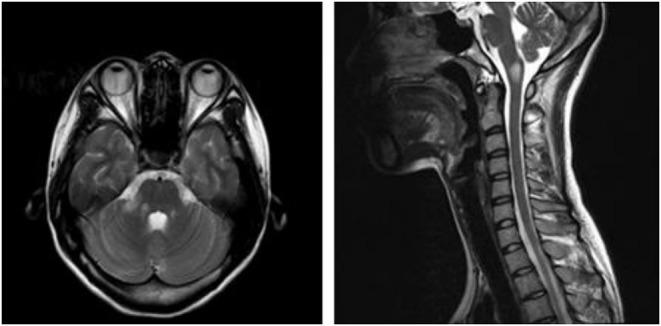

Glial fibrillary acidic protein astrocytopathy is an immunotherapy-responsive autoimmune disease of the central nervous system with various clinical manifestations; among these, there are few reports about area postrema syndrome (APS). The authors present the case of a female patient admitted to the hospital with intractable nausea and vomiting as the predominant symptom. The patient's cerebrospinal fluid was tested by cell-based assays (CBA) and found positive for the presence of anti-glial fibrillary acidic protein (GFAP) antibody, in addition, serological testing showed elevated levels of thyroglobulin and thyroperoxidase-specific antibodies. Brain and cervical MRI showed abnormally high signal on the T2 sequence in the dorsal medulla oblongata and right pontine arm. Therefore, the patient was diagnosed with autoimmune GFAP astrocytopathy. The symptoms improved rapidly after treatment with corticosteroids, and no recurrence has been observed thus far. APS may be a relatively rare clinical manifestation of GFAP astrocytopathy. Importantly, such presentation is challenging to correctly diagnose without typical MRI imaging findings. However, the detection of antibodies in the cerebrospinal fluid or serum may be valuable. Systemic and neurological autoimmunity often coexist, comprehensive antibody screening should be conducted.

胶质纤维酸性蛋白星形细胞病是一种对免疫治疗有反应的中枢神经系统自身免疫性疾病,临床表现多样;其中,关于最后区综合征(APS)的报道较少。作者报告了一例以顽固性恶心和呕吐为主要症状入院的女性患者。对患者的脑脊液进行基于细胞的检测(CBA),发现抗胶质纤维酸性蛋白(GFAP)抗体呈阳性,此外,血清学检测显示甲状腺球蛋白和甲状腺过氧化物酶特异性抗体水平升高。脑部和颈部MRI显示延髓背侧和右桥臂在T2序列上信号异常增高。因此,该患者被诊断为自身免疫性GFAP星形细胞病。使用皮质类固醇治疗后症状迅速改善,迄今为止未观察到复发。APS可能是GFAP星形细胞病相对罕见的临床表现。重要的是,若无典型的MRI影像学表现,这种表现很难正确诊断。然而,脑脊液或血清中抗体的检测可能很有价值。系统性和神经性自身免疫常并存,应进行全面的抗体筛查。